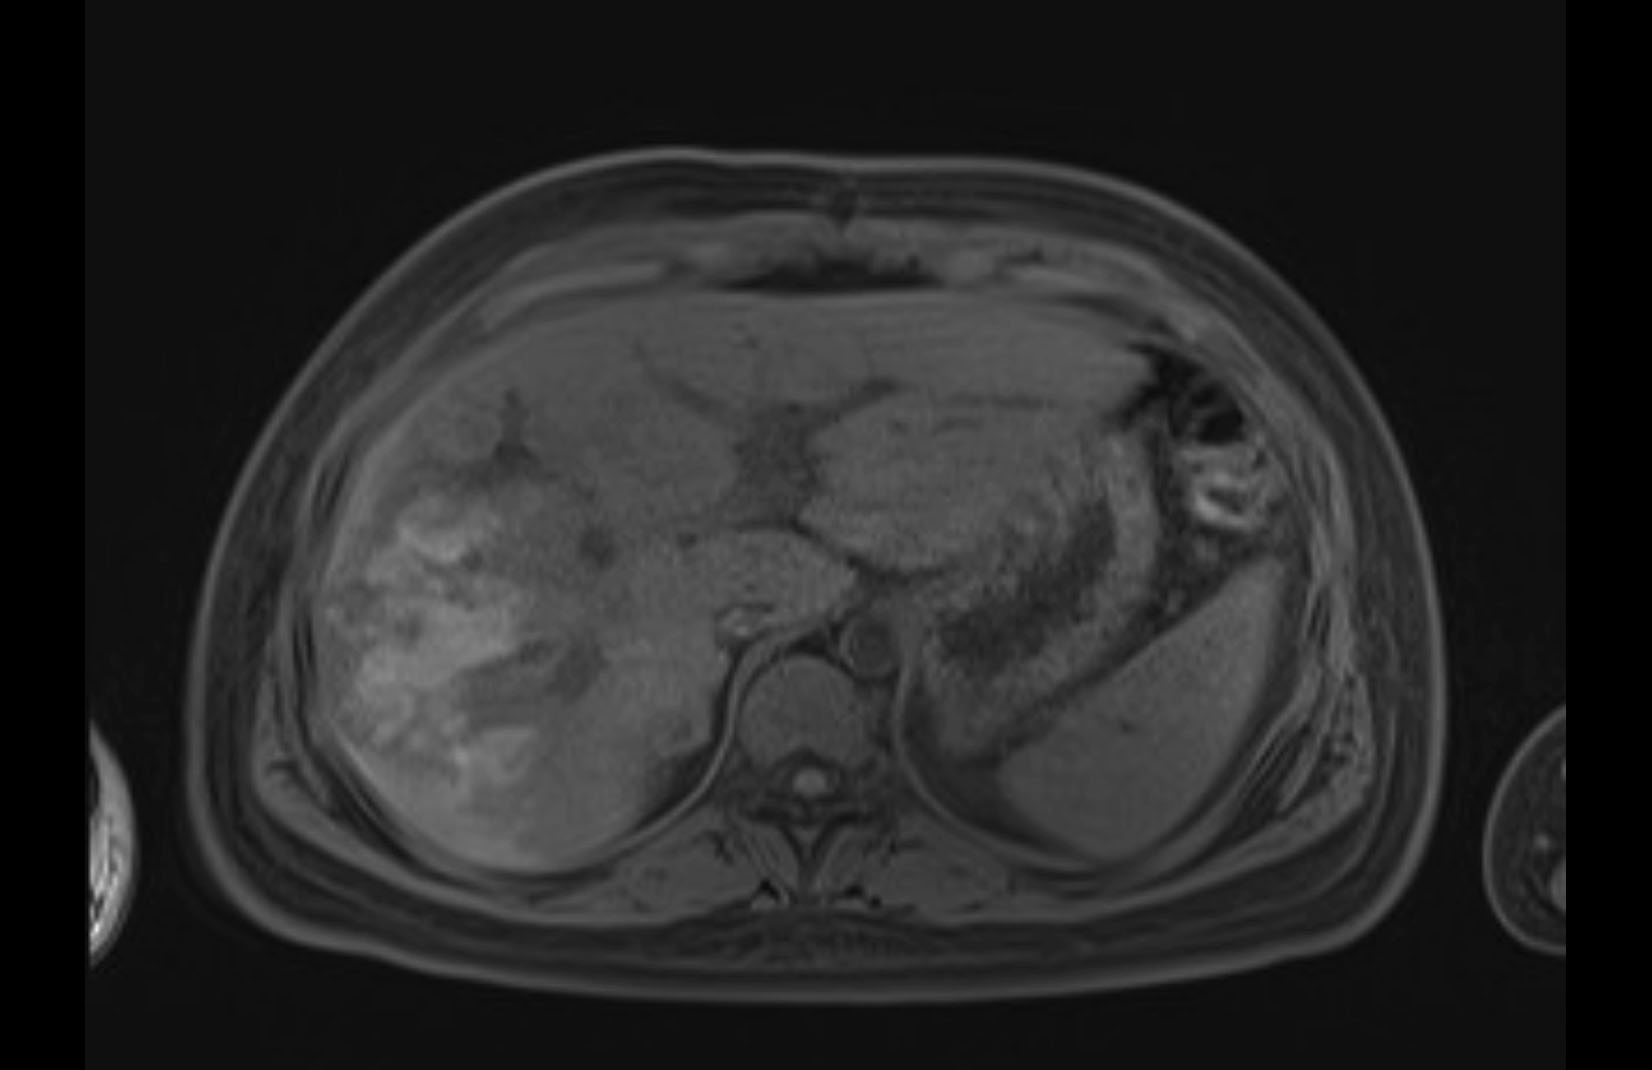

MRI T1

MRI T2

Imaging analysis

Based on initial findings, which issue(s) would you be most concerned about?